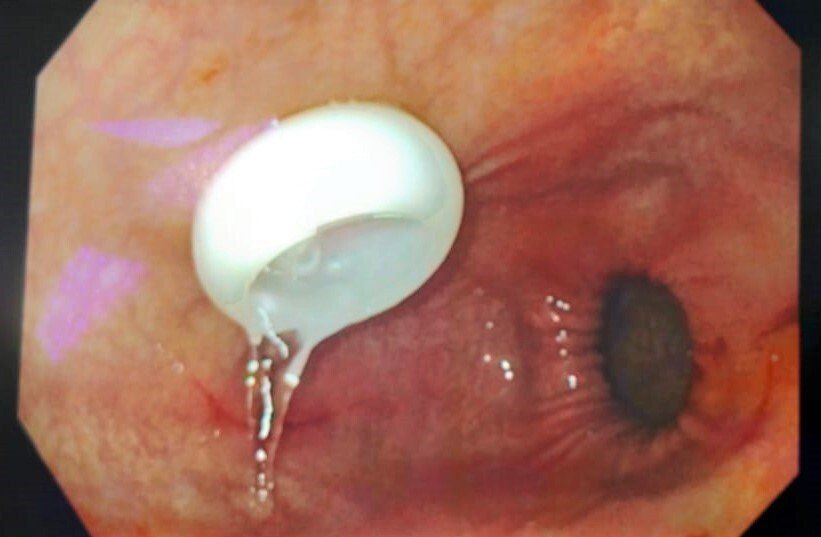

ERCP with pancreatic duct stent placement for chronic pancreatitis patients

20 year young man is a known case of early idiopathic chronic pancreatitis. The patient was admitted with complaints of recurrent upper abdominal pain radiating to the back, with inability to gain weight. Patient underwent ERCP. Pancreato-gram taken suggested dilated PD throughout the head and body, with multiple intraductal pancreatic stones. Balloon sweeps were taken with removal of multiple small white, shiny pancreatic stones. 7 Fr x 10 cm pancreatic stent was inserted. Post procedure there was a significant improvement in the patient’s quality of life with no recurrent pain episodes and weight gain.

Conclusion:

ERCP with PD stenting can improve symptoms in the select group of patients with chronic pancreatitis.